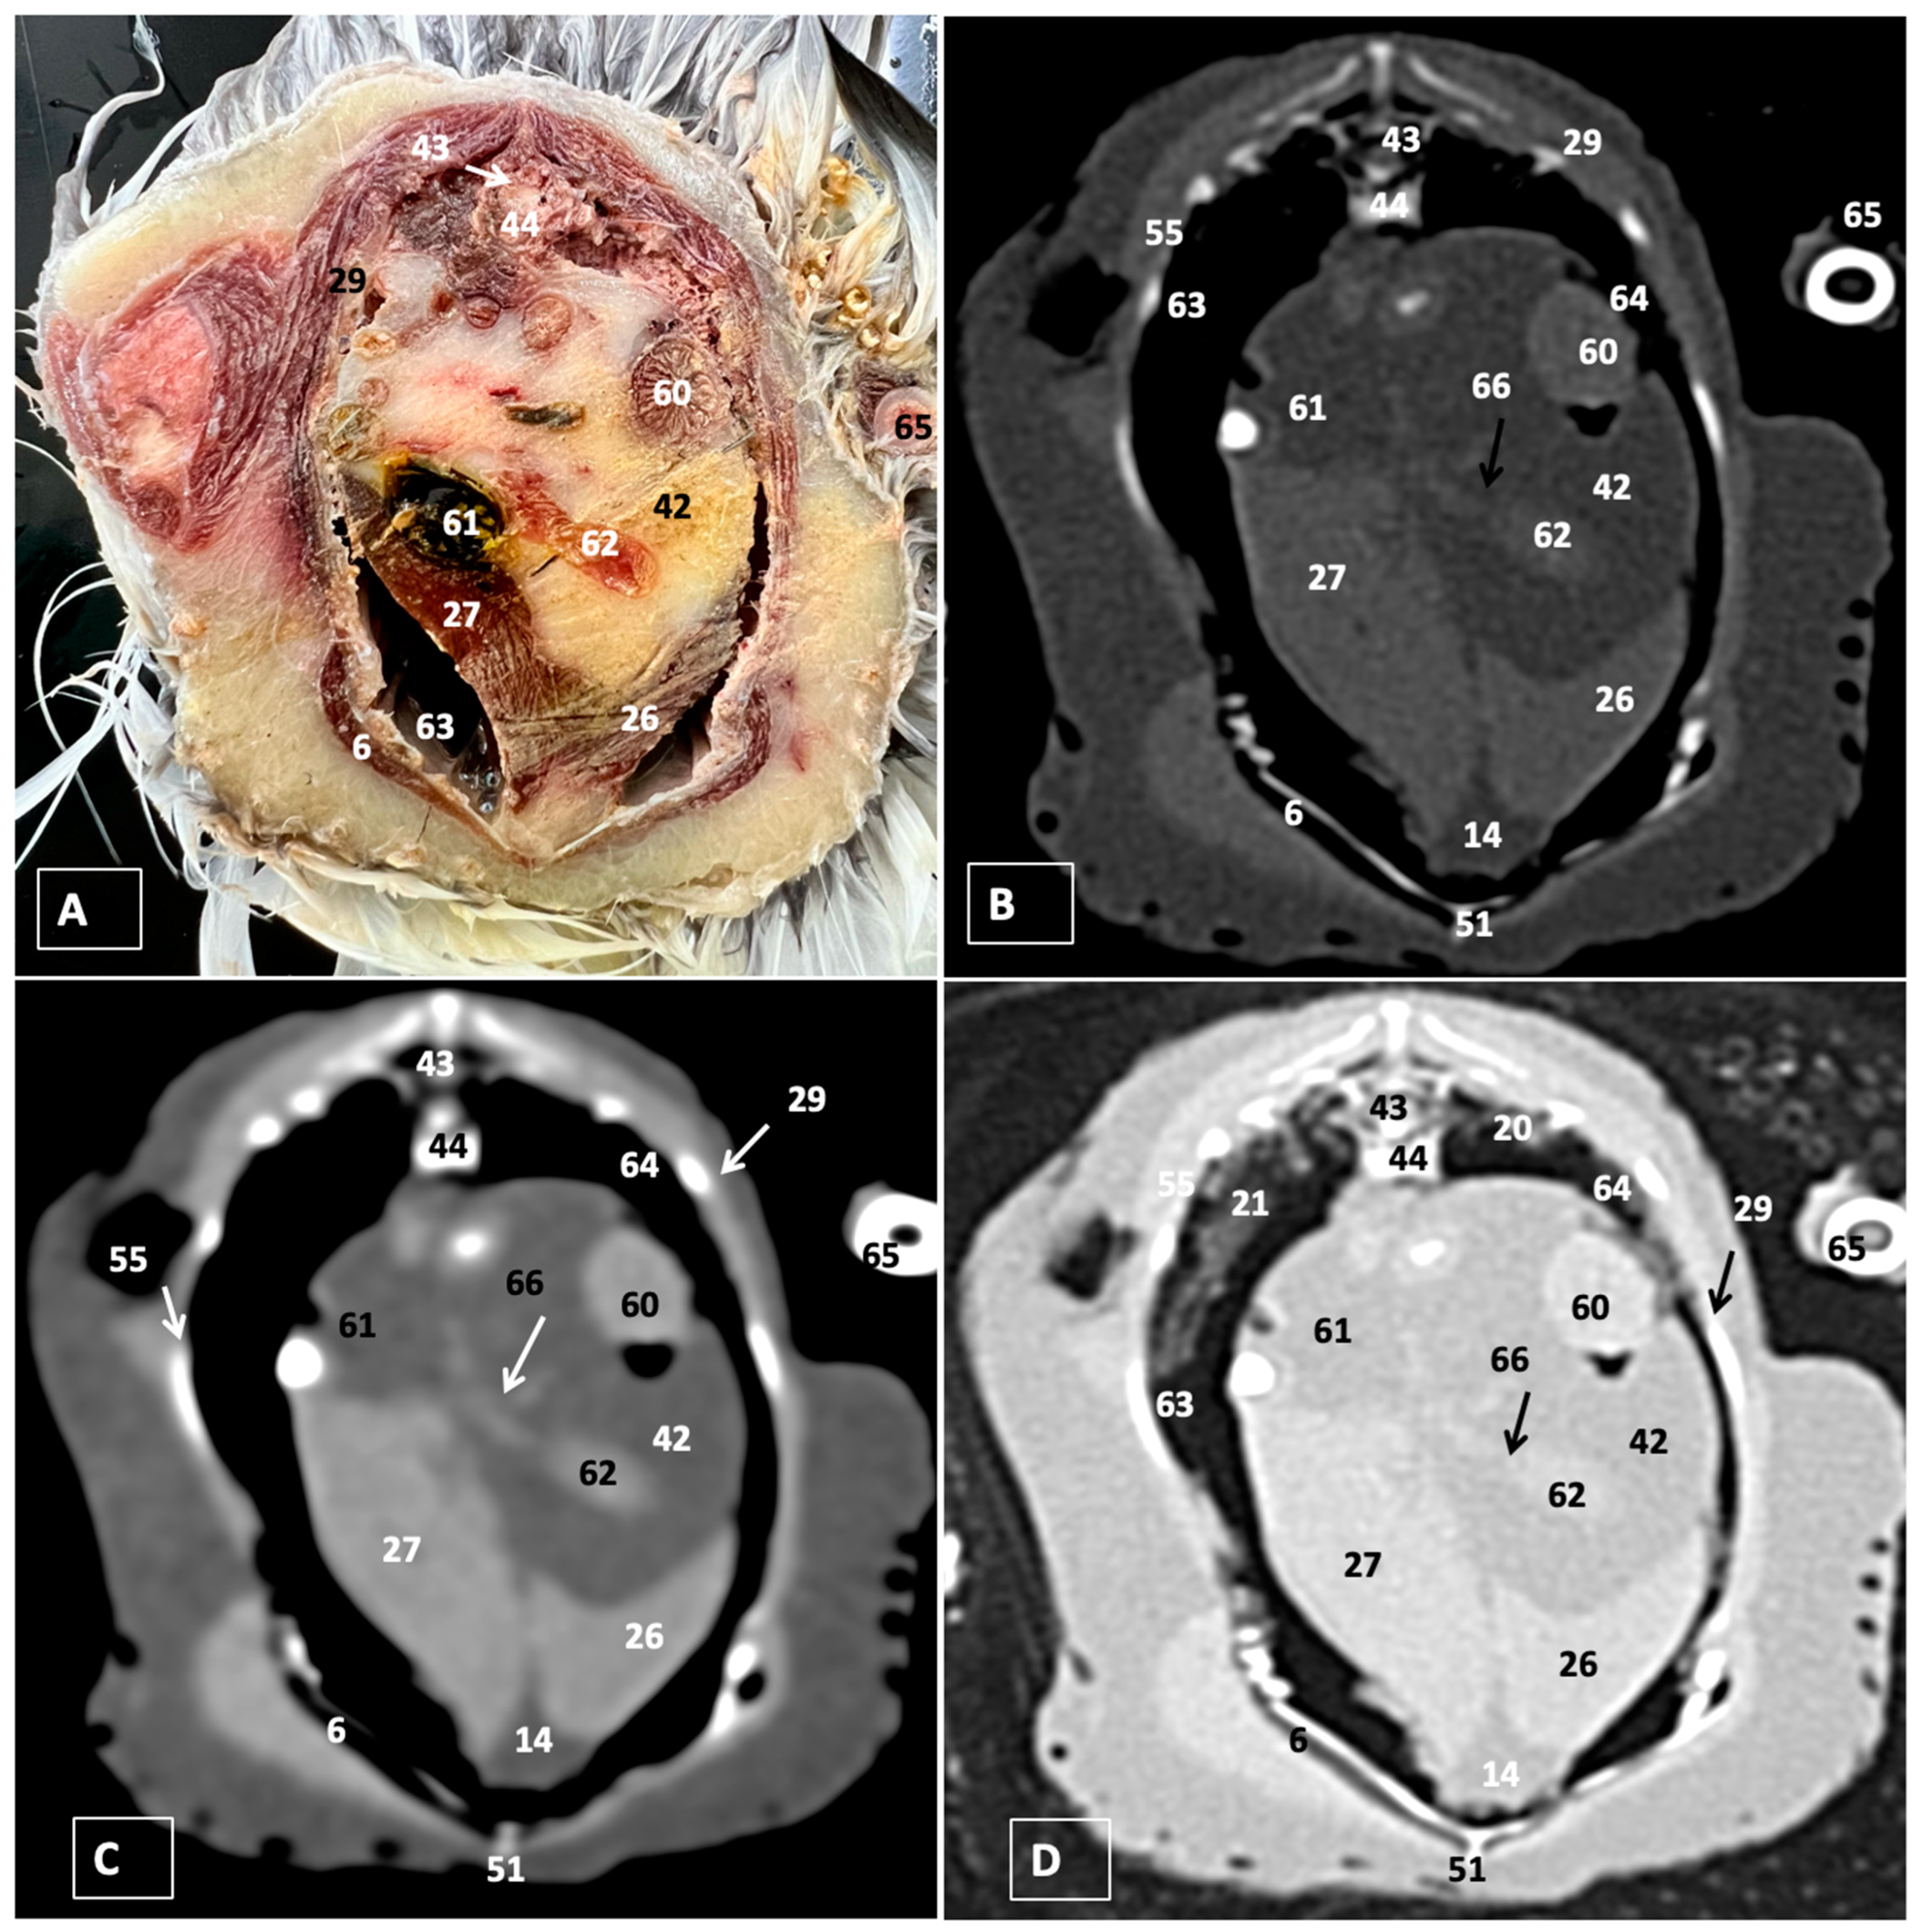

A Cadaveric Study Using Anatomical Cross-Section and Computed Tomography for the Coelomic Cavity in Juvenile Cory’s Shearwater (Aves, Procellariidae, Calonectris borealis)

3. Results

3.1. Anatomical Dissections and Cross-Sections

3.2. Computed Tomography Images